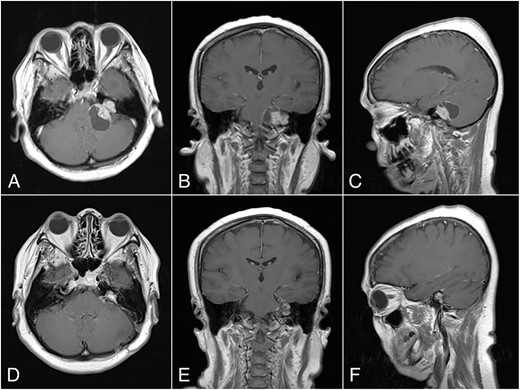

Magnetic resonance imaging (MRI) with contrast revealed a large CPA tumor with two globular segments, one in the cerebellopontine region that compresses the brainstem and the fourth ventricle without hydrocephalus (Fig. 1A–C) and the other is inside the meatus that is suitable for a “dumbbell” vestibular schwannoma.

Preoperative MRI, (A) Axial, (B) Coronal, and (C) Sagittal plane, shows a “dumbbell” shaped vestibular schwannoma. Postoperative MRI, (D) Axial, (E) Coronal, and (F) Sagittal plane, shows near total resection with some residual mass on the left CPA.

The histopathological finding shows the characteristics of a cystic vestibular schwannoma (Fig. 2B and C). Postoperative imaging evaluation using a computed tomography scan revealed no intracranial hemorrhage or hydrocephalus. On the sixth month of evaluation, the patient could do a regular activity without any significant complaints. Postoperative imaging evaluation showed a residual mass surrounding the facial nerve (Fig. 1D–F). After a discussion with the patient, we planned to observe this lesion as it did not cause any significant symptoms.